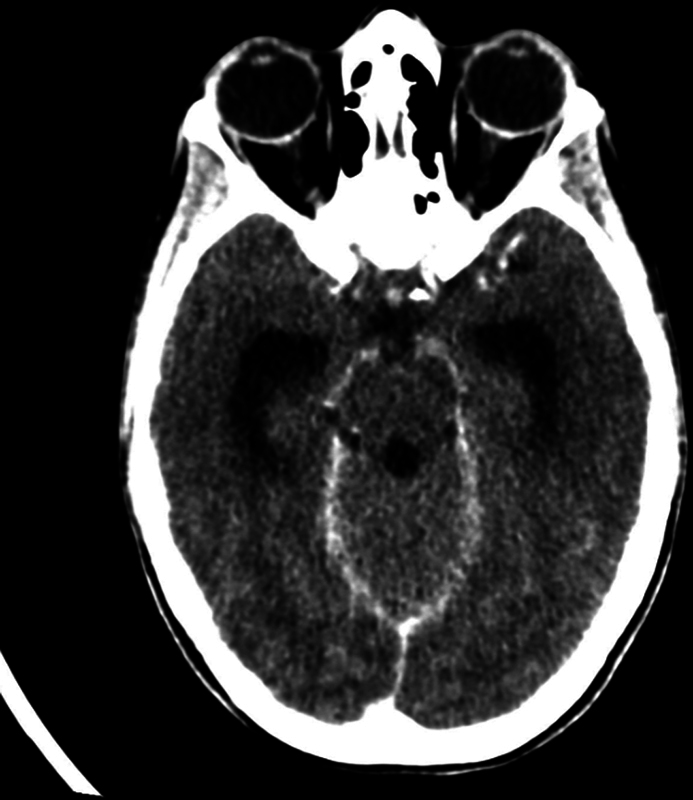

可卡因是苏格兰最常用的消遣性毒品之一,造成重大的社会经济和严重的健康挑战。可卡因引起的中线破坏性病变(CIMDL)的流行率正在上升,由于可卡因的增加。在这里,我们报告一例患者谁发展急性脑积水和脑膜炎作为CIMDL由于长期滥用可卡因的并发症。39岁女性,有慢性鼻用可卡因滥用史,表现为发热、不适和步态不平衡。到达急诊科时,她感觉改变,格拉斯哥昏迷评分(GCS)为10分,左侧偏瘫,需要紧急插管。影像显示急性脑积水及脑水肿。她接受了紧急脑室外引流术(EVD)以缓解颅内压升高。她的一系列问题和生化参数指向急性细菌性脑膜炎的诊断。她的血液培养培养出对甲氧西林敏感的金黄色葡萄球菌,她开始使用广谱抗生素。她的计算机断层扫描显示蝶窦内有空气,斜坡侵蚀,C1前弓部分侵蚀,符合CIMDL。她发展为后循环缺血性中风,这是由于她的心内膜炎和经胸超声心动图检测到的三尖瓣赘生物。最终,她接受了脑室腹腔分流术以永久转移脑脊液。神经学评分为E4V5M6,出院时伴有左侧偏瘫。她正在口腔颌面外科、耳鼻喉科和颅底小组的护理下积极康复。该病例强调了多学科护理和支持在管理此类病例中的重要性,特别是旨在防止感染复发导致显著发病率甚至死亡率。

Cocaine is among the most commonly used recreational drugs in Scotland, contributing to significant socioeconomic and severe health challenges. The prevalence of cocaine-induced midline destructive lesions (CIMDL) is rising due to increased cocaine insufflation. Here, we report a case of a patient who developed acute hydrocephalus and meningitis as complications of CIMDL due to long-term cocaine abuse. A 39-year-old woman with a history of chronic nasal cocaine abuse presented with fever, malaise, and gait imbalance. On arrival at accident and emergency department, she had altered sensorium, Glasgow coma scale (GCS) of 10, and left-sided hemiparesis, requiring emergency intubation. Imaging revealed acute hydrocephalus and brain edema. She underwent an emergency external ventricular drain (EVD) to temporize her raised intracranial pressure. Her constellation of problems and biochemical parameters directed toward a diagnosis of acute bacterial meningitis. Her blood cultures grew methicillin-sensitive Staphylococcus aureus , and she was started on broad-spectrum antibiotics. Her computed tomography scans showed air in the sphenoid sinus, clival erosion, and partial erosion of the anterior arch of C1, consistent with CIMDL. She developed posterior circulation ischemic strokes, which were attributed to her endocarditis and tricuspid valve vegetations that were detected on her transthoracic echocardiogram. Eventually, she underwent a ventriculoperitoneal shunt for permanent cerebrospinal fluid diversion. Neurologically, she was E4V5M6 with residual left hemiparesis at the time of discharge. She is on aggressive rehabilitation under the care of oral maxillofacial surgery, otorhinolaryngology, and a skull base team for her CIMDL. This case highlights the importance of multidisciplinary care and support in managing such cases, especially aiming to prevent the recurrence of infection leading to significant morbidity or even mortality.